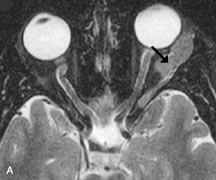

Muscle Disorders

Extraocular muscle enlargement in patients with thyroid-associated orbitopathy is demonstrated equally well with CT and MRI studies. However, the superior tissue contrast on MR images reveals better details of the relationships of the optic nerve to the thickened muscles at the orbital apex (Fig. 16).50 In addition, MRI may be able to differentiate between muscles that are enlarged as a result of edema and active inflammation and those enlarged because of fibrosis by their T2 relaxation times.21 Quantitative MRI was not found to be accurate in predicting the success of low-dose orbital irradiation.51 However, a muscular index relating the diameters of the rectus muscles to the bony orbital dimensions was useful in predicting optic nerve compression.52

Fig. 16. A-C, T1-weighted MR scans obtained with a high-resolution surface coil demonstrate fusiform enlargement of the extraocular muscles. The medial, lateral, and inferior rectus muscles are especially involved. Note the relative sparing of the tendinous insertions, a finding characteristic of this disease process, as well as fatty infiltration of the lateral and inferior rectus muscles. There is marked proptosis, best visualized on the sagittal image (A), and mild crowding of the optic nerve at the orbital apex.